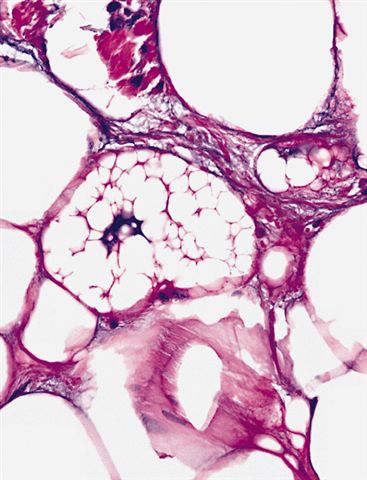

Contributed by Michael Clay, M.D., Melanie Bourgeau, M.D. and AFIP

Morphologic variability:

Metaplastic change:

- Sclerosing subtype

- Second most common subtype

- Predilection for retroperitoneal or paratesticular location

- Collagenous fibrous tissue with scattered adipocytes and atypical multinucleated stromal cells

- Scant lipogenic component may be missed in small samples